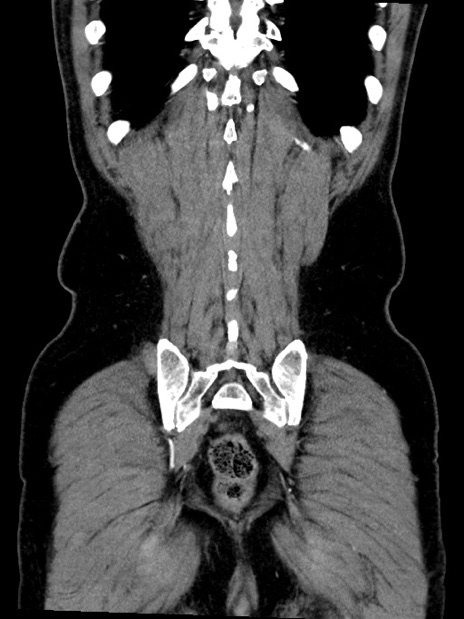

症例35(冠状断像)

【症例】70歳代 男性

【主訴】腹部膨満、嘔吐

【現病歴】昨日より腹部膨満感出現。本日増悪し、仙痛出現。嘔吐あり、受診。

【既往歴】糖尿病、胆摘後

【身体所見】BP 149/80mmHg、HR 74/min、BT 35.9℃、腹部:膨満、軟、圧痛なし。腸雑音減弱あり。上腹部正中切開瘢痕あり。

【データ】WBC 13500、CRP 1.72

横断像